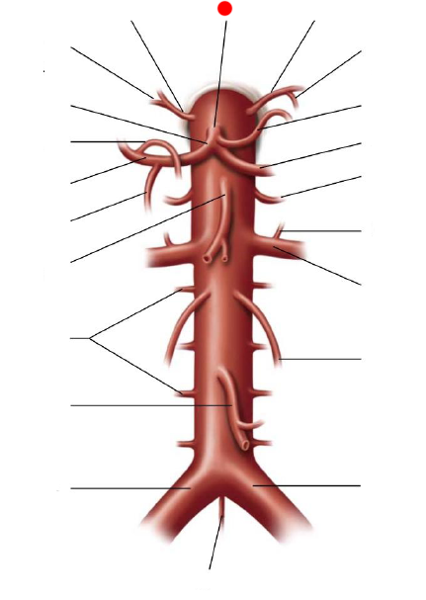

Aortic Arch

Ascending/descending aorta

Brachiocephalic artery

Celiac trunk

Common hepatic artery

Common iliac artery/vein

Gonadal (=testicular/ovarian) artery/vein

Internal/external iliac artery/vein

Left gastric artery/vein

Renal artery/vein

Splenic artery/vein

Subclavian artery/vein

Superior/inferior mesenteric artery

Superior/inferior vena cava

Thoracic aorta

Abdominal Aorta

Vertebral artery